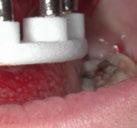

En las piezas 16 y 17 el paciente presentaba restauraciones atornilladas de metalcerámica sobre implantes oseointegrados. Se planificó realizar estas en una fase posterior a la rehabilitación de las piezas dentarias mediante flujo digital con bases de titanio y cuerpos de escaneo.

SW 5.2, Dentsply Sirona) (Figuras 22-27), la cual fue materializada en dos tipos de materiales a partir de bloques cerámicos IPS Empress CAD y cerámica vítrea de disilicato de litio IPS E.max CAD (Figuras 28-30)

Finalmente, las restauraciones se cementaron adhesivamente (Figuras 31-35). En las piezas 16 y 17 se realizaron restauraciones cementoatornilladas como última fase de tratamiento. Se recomendó al paciente una férula de protección superior la cual fue elaborada mediante un flujo de trabajo digital (Figura 36)